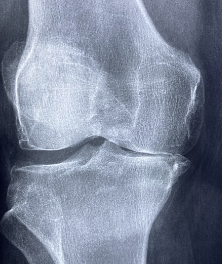

글루코사민 콘드로이친 msm 효능 및 부작용 적정섭취량 알아봐요 글루코사민 콘드로이친 msm 효능 및 부작용 적정섭취량 등 관련 정보 알아보도록 하겠습니다. 관절은 뼈와 뼈 사이에 위치한 연결점으로, 우리 몸을 움직이기 위한 중요한 부분입니다. 관절은 뼈의 끝에 위치한 연골과 뼈를 연결하는 인대로 이루어져 있으며, 이러한 구조는 원활한 움직임을 가능하게 합니다. 하지만 연령이 들어가거나 부상 등으로 인해 관절의 기능이 손상되면 관절염과 같은 질환으로 발생할 수 있습니다. 이러한 질환은 관절 통증, 감각 이상, 염증 및 손상 등을 일으키며, 일상생활에서의 움직임과 활동에 지장을 주어 생활의 질을 저하시킵니다. 이에 따라 적절한 치료와 예방이 필요하며, 영양소와 운동 등을 통한 관리가 중요합니다.

글루코사민은 연골을 유지하는 데 필요한 성분으로, 연골 조직의 생산과 수리를 돕습니다. 또한 관절염 등의 관절 질환으로 인한 통증 및 염증을 완화하는데도 효과적입니다. 또한 연골 조직의 건강을 유지함으로써, 무릎 퇴행성 질환의 발생을 예방하고 뼈 건강에도 도움을 줄 수 있습니다.